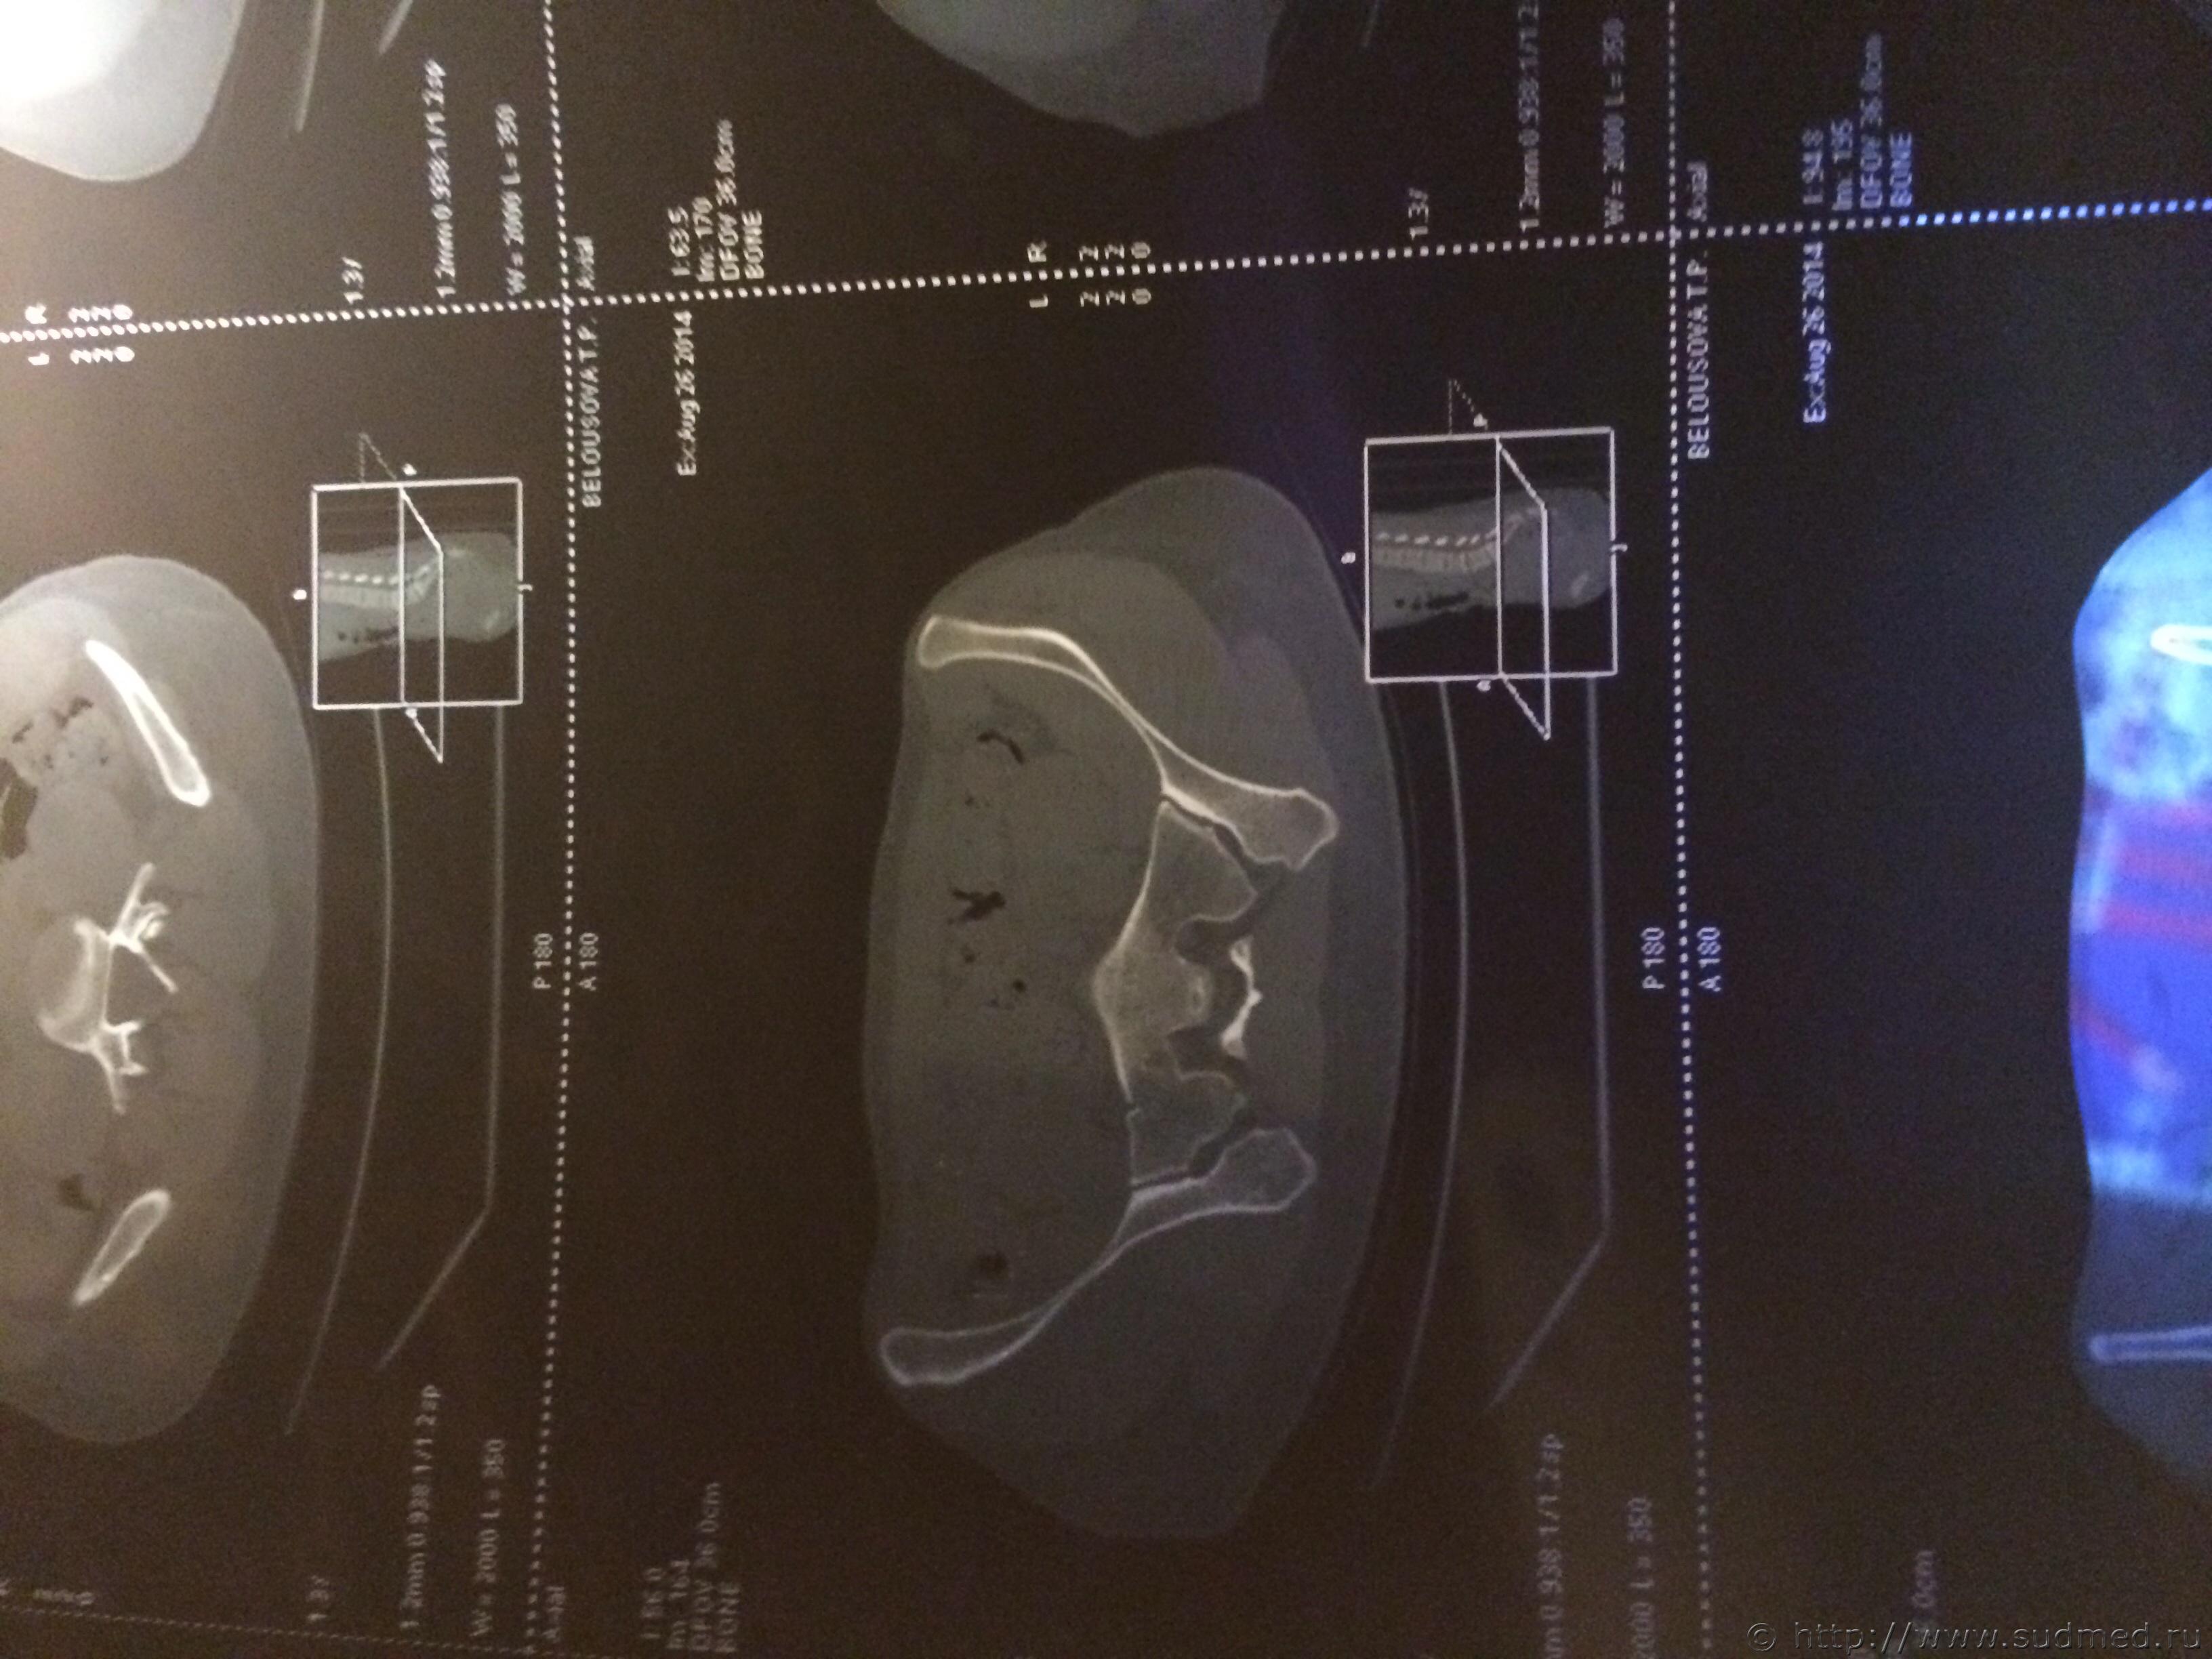

Спасибо! У меня результаты КТ, ошиблась)

КТ

Как мне видится - вертикальный перелом крестца. Тяжкий вред.

Впрочем, оставляю небольшую вероятность, что я не видел все сканы, да и качество их здесь, разумеется, хуже, чем изображение на пленке или на экране компьютера у врача, работающего на томографе.